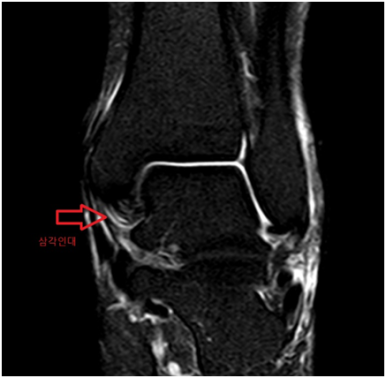

발목 MRI에서 바깥쪽 인대를 구성하는 전거비인대, 후거비인대에 심한 손상, 안쪽 인대를 구성하는 삼각인대 손상, 발목 경비인대결합 손상으로 수술이 가능한 정형외과 병원으로 전원하였습니다.

• MRI 검사: 인대 손상 MRI 검사: 인대 손상